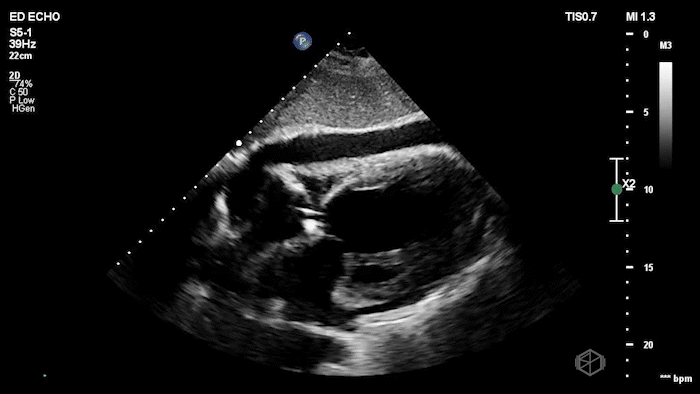

RV diastolic collapse

17 - What is the abnormality?

Atrial septal aneurysm